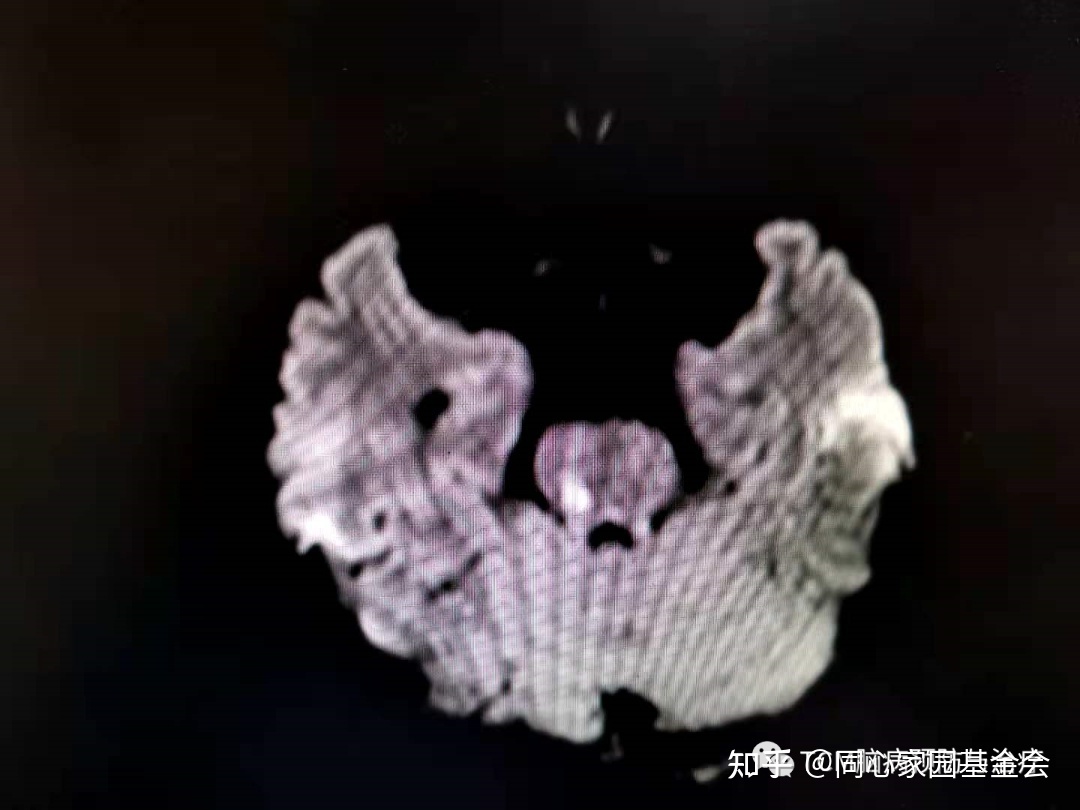

门诊查颅脑MRI如下:

诊断:急性脑梗死(桥脑),收入住院治疗,以急性脑梗死方案对症治疗。